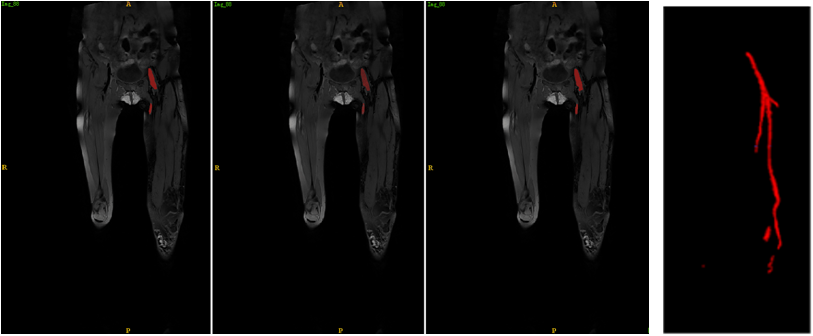

3. 本解决方案比已有方法相比可以实现血栓更精准的自动分割,实现血栓特性的自动定量和立体可视化分析